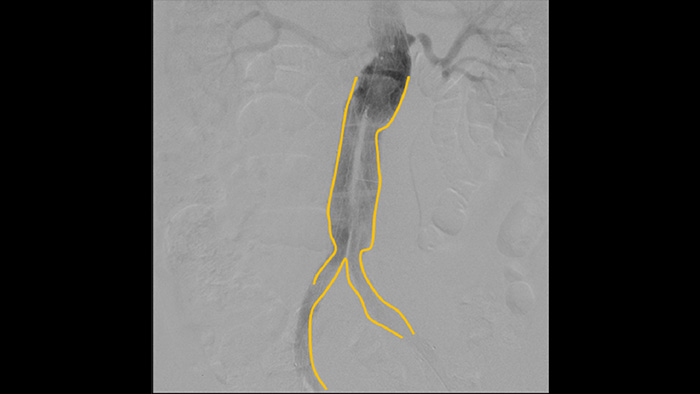

Use the Outlining tool to easily mark a bifurcation or side branches by simply drawing on the monitor of the Mobile Viewing Station with your finger or an externally connected mouse.

Digital subtraction angiography (DSA) is used in interventional vascular procedures to clearly visualise blood vessels by removing structures that can obscure vessel visibility. Roadmap fluoroscopy overlays a previously acquired subtracted contrast image on the live fluoroscopy, allowing you to track a device without reinjecting contrast.

Enhance visibility of tortuous vasculature with Iodine and CO2 contrast medium options. Easily control injections at table side. For patients with renal failure, you can use the CO2 option to easily visualise small vessels without using iodine contrast.